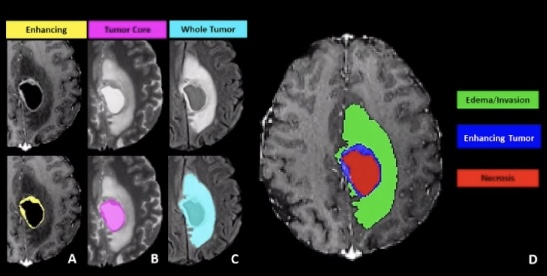

Brain tumor segmentation은 뇌종양에 해당하는 영역을 MRI 영상에서 구분하는 일인데, 지금도 병원에서는 수작업으로 많이 진행하고 있다. 우리가 개발한 딥러닝 네트워크는 이를 자동화하는 방식이다.

멀티모달(Multi-modal) MRI data를 기반으로 뇌종양을 가장 정확히 구획화(Segmentation)하는 딥러닝 네트워크 개발 대회다. 전 세계에서 매년 개최하는 대회로 올해 10회째다. 특히 올해 BRATS 대회는 국제적으로 영향력 있는 학회 RSNA(Radiological Society of North America), MICCAI(Medical Image Computing and Computer Assisted Intervention), ASNR(American Society of Neuroradiology)가 공동 주관해 더 주목받았다.

올해는 ‘뇌종양 인공지능 대회(Brain Tumor AI Challenge)’가 주제다. 세부적으로는 ▲뇌종양 구획화(Brain Tumor Segmentation) ▲뇌종양방사능유전체학분석(Brain Tumor Radiogenomic Classification)로 나눴다.